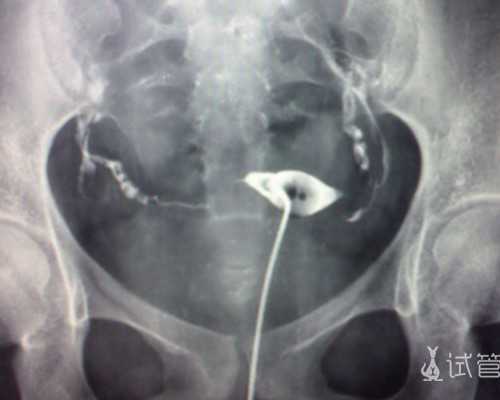

香港验血测男女首要是以DNA基因检测,检测胎儿游离的DNA中是否含有Y染色体,因为只需男性才会有Y染色体,这样能够准确直接的判别男孩女...